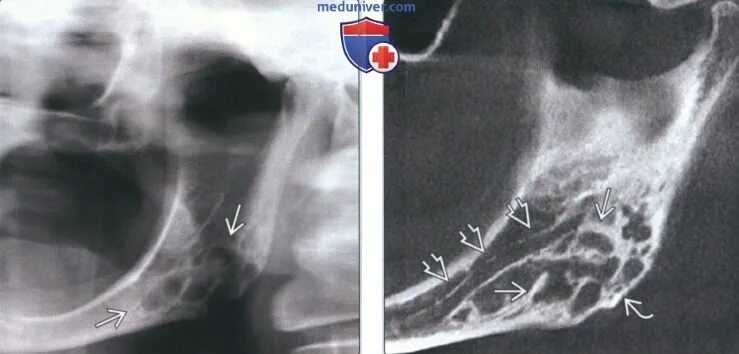

Фиброма кт